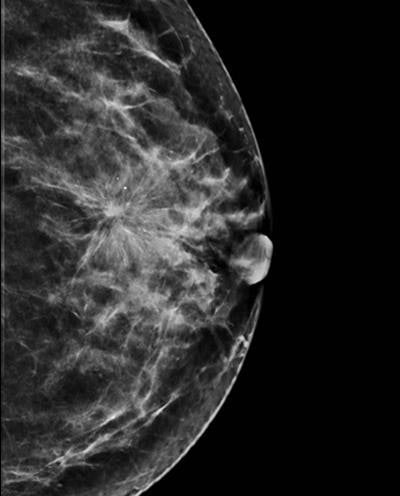

Image synthétique reconstruite à partir des coupes de tomosynthèse. Toutes les images sont reproduites avec l'aimable autorisation de Dr Luc Ceugnart.Plutôt que d'utiliser le protocole complet EUREF (Organisation européenne de référence pour les services de dépistage et de diagnostic du cancer du sein de qualité garantie) pour la DBT, le contrôle de la qualité en France mettra en œuvre un protocole identique pour la mesure de la dose, mais sans mettre en œuvre les protocoles de contrôle de qualité de l'image, selon le Dr Ceugnart.

Présentant un aperçu de la revue de la littérature lors des JFR 2019, Ceugnart a déclaré que la combinaison de la mammographie et de la DBT semblait produire de meilleurs taux de détection que la mammographie seule. Cependant, des études complémentaires sont nécessaires pour obtenir des résultats plus robustes, notamment en termes de taux de cancer d'interval. Il a également évoqué la possibilité d'images de synthèse générées à partir d'ensembles de données DBT afin d'éviter une exposition supplémentaire aux radiations.